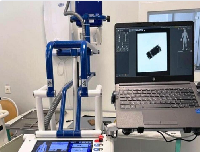

Мобильный рентгенаппарат + оцифровщик. Получение рентгеновского изображения на экране ноутбука. Вариант за 1,4 миллиона рублей под ключ.

Мобильный рентгенаппарат с печатью рентгенограмм на рентгеновской пленке. Цена 700000 рублей.